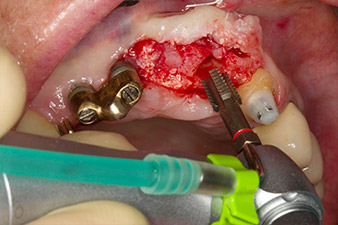

matériau de substitution osseuse xénogénique

Fig. 5 : Pour que le tissu péri-implantaire soit de la meilleure qualité possible, le site a subi une augmentation supplémentaire avec matériau de substitution osseuse xénogénique et membrane collagène dans le cadre d'une régénération osseuse guidée.